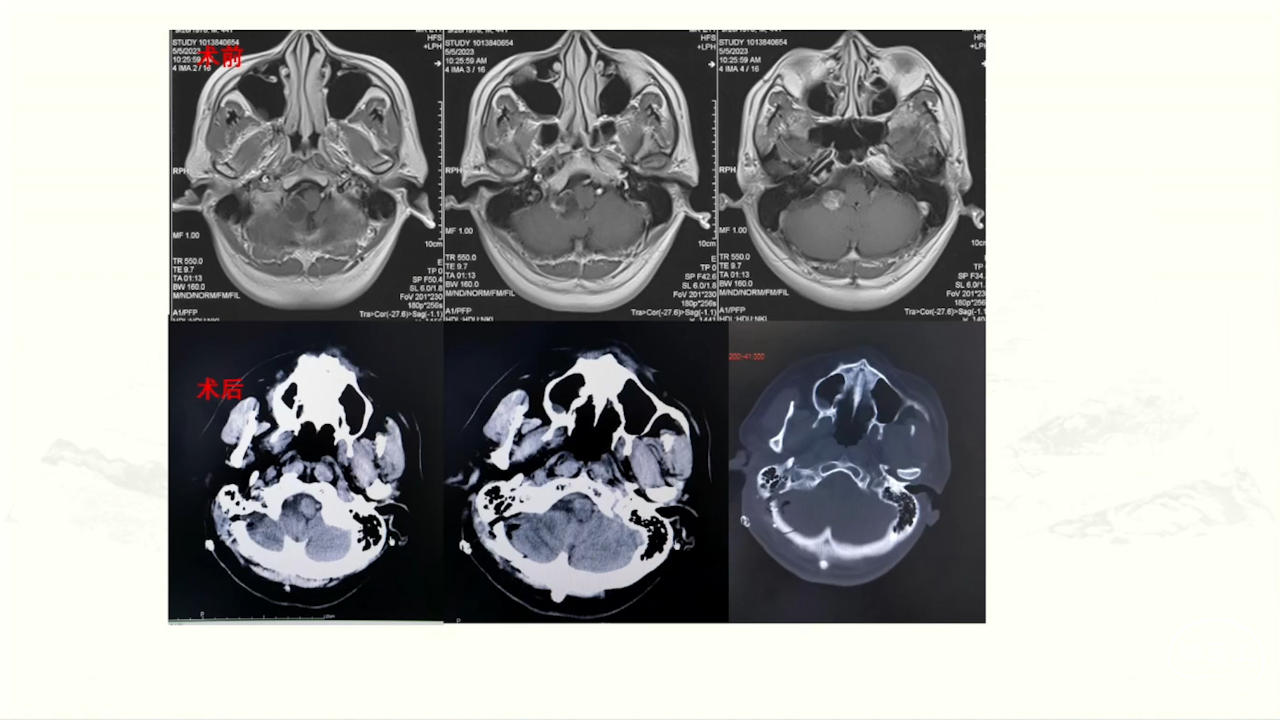

颈静脉孔区肿瘤充分显露是硬道理。肿瘤越大,工作通道越宽。颈静脉孔扩大越明显,开放颈静脉孔越容易。

卜博教授:颈静脉孔区肿瘤:解剖及156例经验